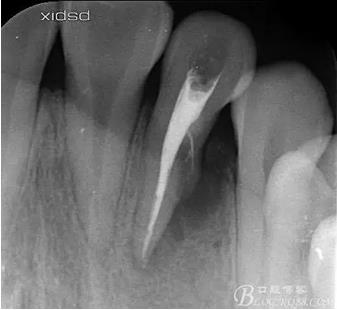

(1) 檢查:12唇側(cè)牙齦可見竇道,牙體顏色較鄰牙暗,無光澤,形態(tài)完整無缺損,唇側(cè)及近遠中向未提及牙周袋。腭側(cè)齦緣輕度紅腫,舌側(cè)窩可探及裂溝,可見浸墨狀痕跡,沿裂溝舌側(cè)探診牙周袋深大于11mm,除患牙外全口牙周狀況良好,為探及牙周袋,牙齦色粉紅。邊緣菲薄,質(zhì)地堅韌。12冷熱診無反應,叩診(+-),無明顯松動,無咬合創(chuàng)傷。12根尖x線片示,根管中三分之一中可見一斜向線樣透射影像根尖區(qū)及遠中根三分之一可見低密度透射暗影,錐形束CT示12根尖區(qū)唇腭向骨吸收已穿通,根面溝達根中三分之一卷曲分出另一牙根,再未見其他明顯的根管系統(tǒng)。

(6)復診:原暫封材料再位,牙周無明顯異常與不適,常規(guī)清潔根管,H銼清除根管內(nèi)維他,次氯酸鈉終末消毒,干燥根管,單尖測壓發(fā)充填根管,術(shù)后拍片到位。